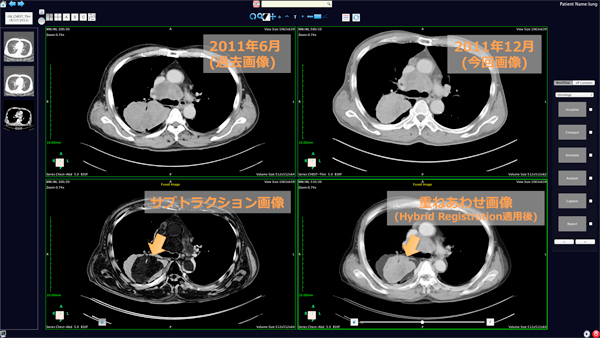

Phoenixの開発においては,PACSと連携した画像診断ビューアとしての機能を満たすだけでなく,最先端のフュージョンアルゴリズムを搭載する事で撮影日や画像の種類が異なっていても,正確かつ自動で画像位置合わせができることを目指しました。撮影日や撮影法が異なる画像の比較する読影者としての基本的な作業の効率を向上させることができます。Phoenixは,Patient Centricビューアというコンセプトに基づき,患者様主体の統合型レポートの作成が可能となります。また,ユーザの作業手順を記憶し誘導するワークフロー機能を搭載し,臨床現場での生産性が向上することが期待されます。AZE独自開発のハイブリッドレジストレーションを採用し,ボタンひとつで過去画像やモダリティの異なる画像の画像統合がされ,疾患の経時的変化を即座に確認する事ができます。最先端の画像処理アルゴリズムを取り入れながら開発が行われており,常に製品の革新度を追求していく製品となっています。